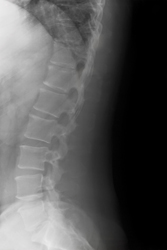

Spinal cord lesions are usually the result of trauma from injury but can be due to tumours, degenerative diseases or congenital conditions. Successful treatment often requires investigation of the affected area by insertion of a microendoscope into the area surrounding the spinal cord. The subarachnoid space is the cavity between between the arachnoid and the pia mater. The meninges consist of three layers: the dura mater, the arachnoid mater, and the pia mater. Members of the European project MINOSC made it their aim to develop a flexible microendoscope to visually assess the lesions and to operate simultaneously with associated equipment. In order to fulfil this objective, the physical, anatomical and physiological properties of the subarachnoid space must be analysed to ensure the accurate manoeuvrability of the endoscope. Project partners at Technion, the Israel Institute of Technology, specifically researched previously uncharted areas of the thoracic subarachnoid space. Magnetic resonance imaging (MRI) scans from 42 patients were merged to produce data on the dimensions of the spinal cord and the volume and shape of the dural sac and the subarachniod space. These were taken at mid- and inter-vertebral disc levels to produce a complete map. The measurements match those available from previous studies. They were recorded for the transversal plane which cuts the body into top and bottom portions. A low level of variance was evident as there was a high degree of symmetry. Another story was revealed in the sagittal plane however. Dividing the body into right and left portions, in the median plane, there was found to be a very significant coefficient of variation (as high as 42%). The findings in this study not only increase the knowledge of the structure of the spinal cord. The models also dictate the maximum dimensions of the endoscope so that it can perform accurate movements in the subarachnoid space. This will no doubt increase the success of surgery for those with spinal cord lesions.